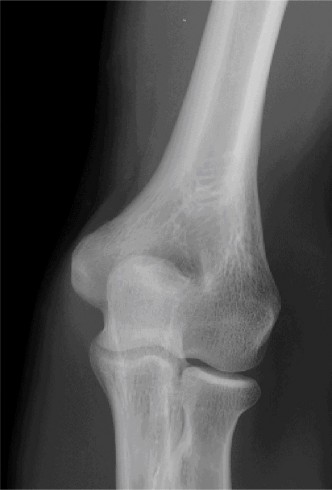

Physicians should obtain a complete set of x-rays. Special views include the modified Westpoint axillary (Fig. 2–43B) to evaluate for glenoid loss and the stryker notch view (Fig. 2–43A) to evaluate the Hill–Sachs lesion. This view brings the posterolateral defect into direct visualization. 3D CT imaging is also very useful for evaluating glenoid bone loss and estimating the size of the Hill–Sachs lesion.

--- _Figure 2–43_A: Stryker notch view. B: West point axillary view. (From Bucholz RW and Heckman JD. Rockwood and Green’s Fractures in Adults 7e. Philadelphia: Wolters Kluwer, 2009.)